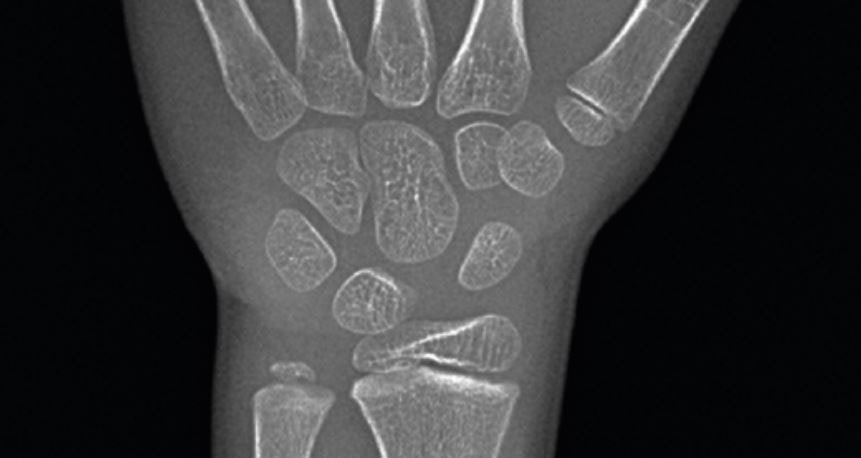

![연세굿데이치과] 성장판 검사가 중요한 이유 관련 이미지 4](https://pub-9f2bb3498faf4d1d8714b41df24753e3.r2.dev/content/clinics/archive/5hurea2jnb/naver_blog/eunkyo3370/assets/by_hash/ded0145bd5580436f268e855c39adc63c754df775f0a38bb1ab4139bf5904b90.jpg)

(닫힌 성장판)

성장판은 뼈의 끝부분에 있는 연골조직인데요.

성장기에는 연골세포가 분화하여 키가 자라지만

사춘기에 접어들면 뼈성숙이 빨라지면서

연골이 딱딱한 뼈로 바뀌어 성장판이 닫히게 됩니다.